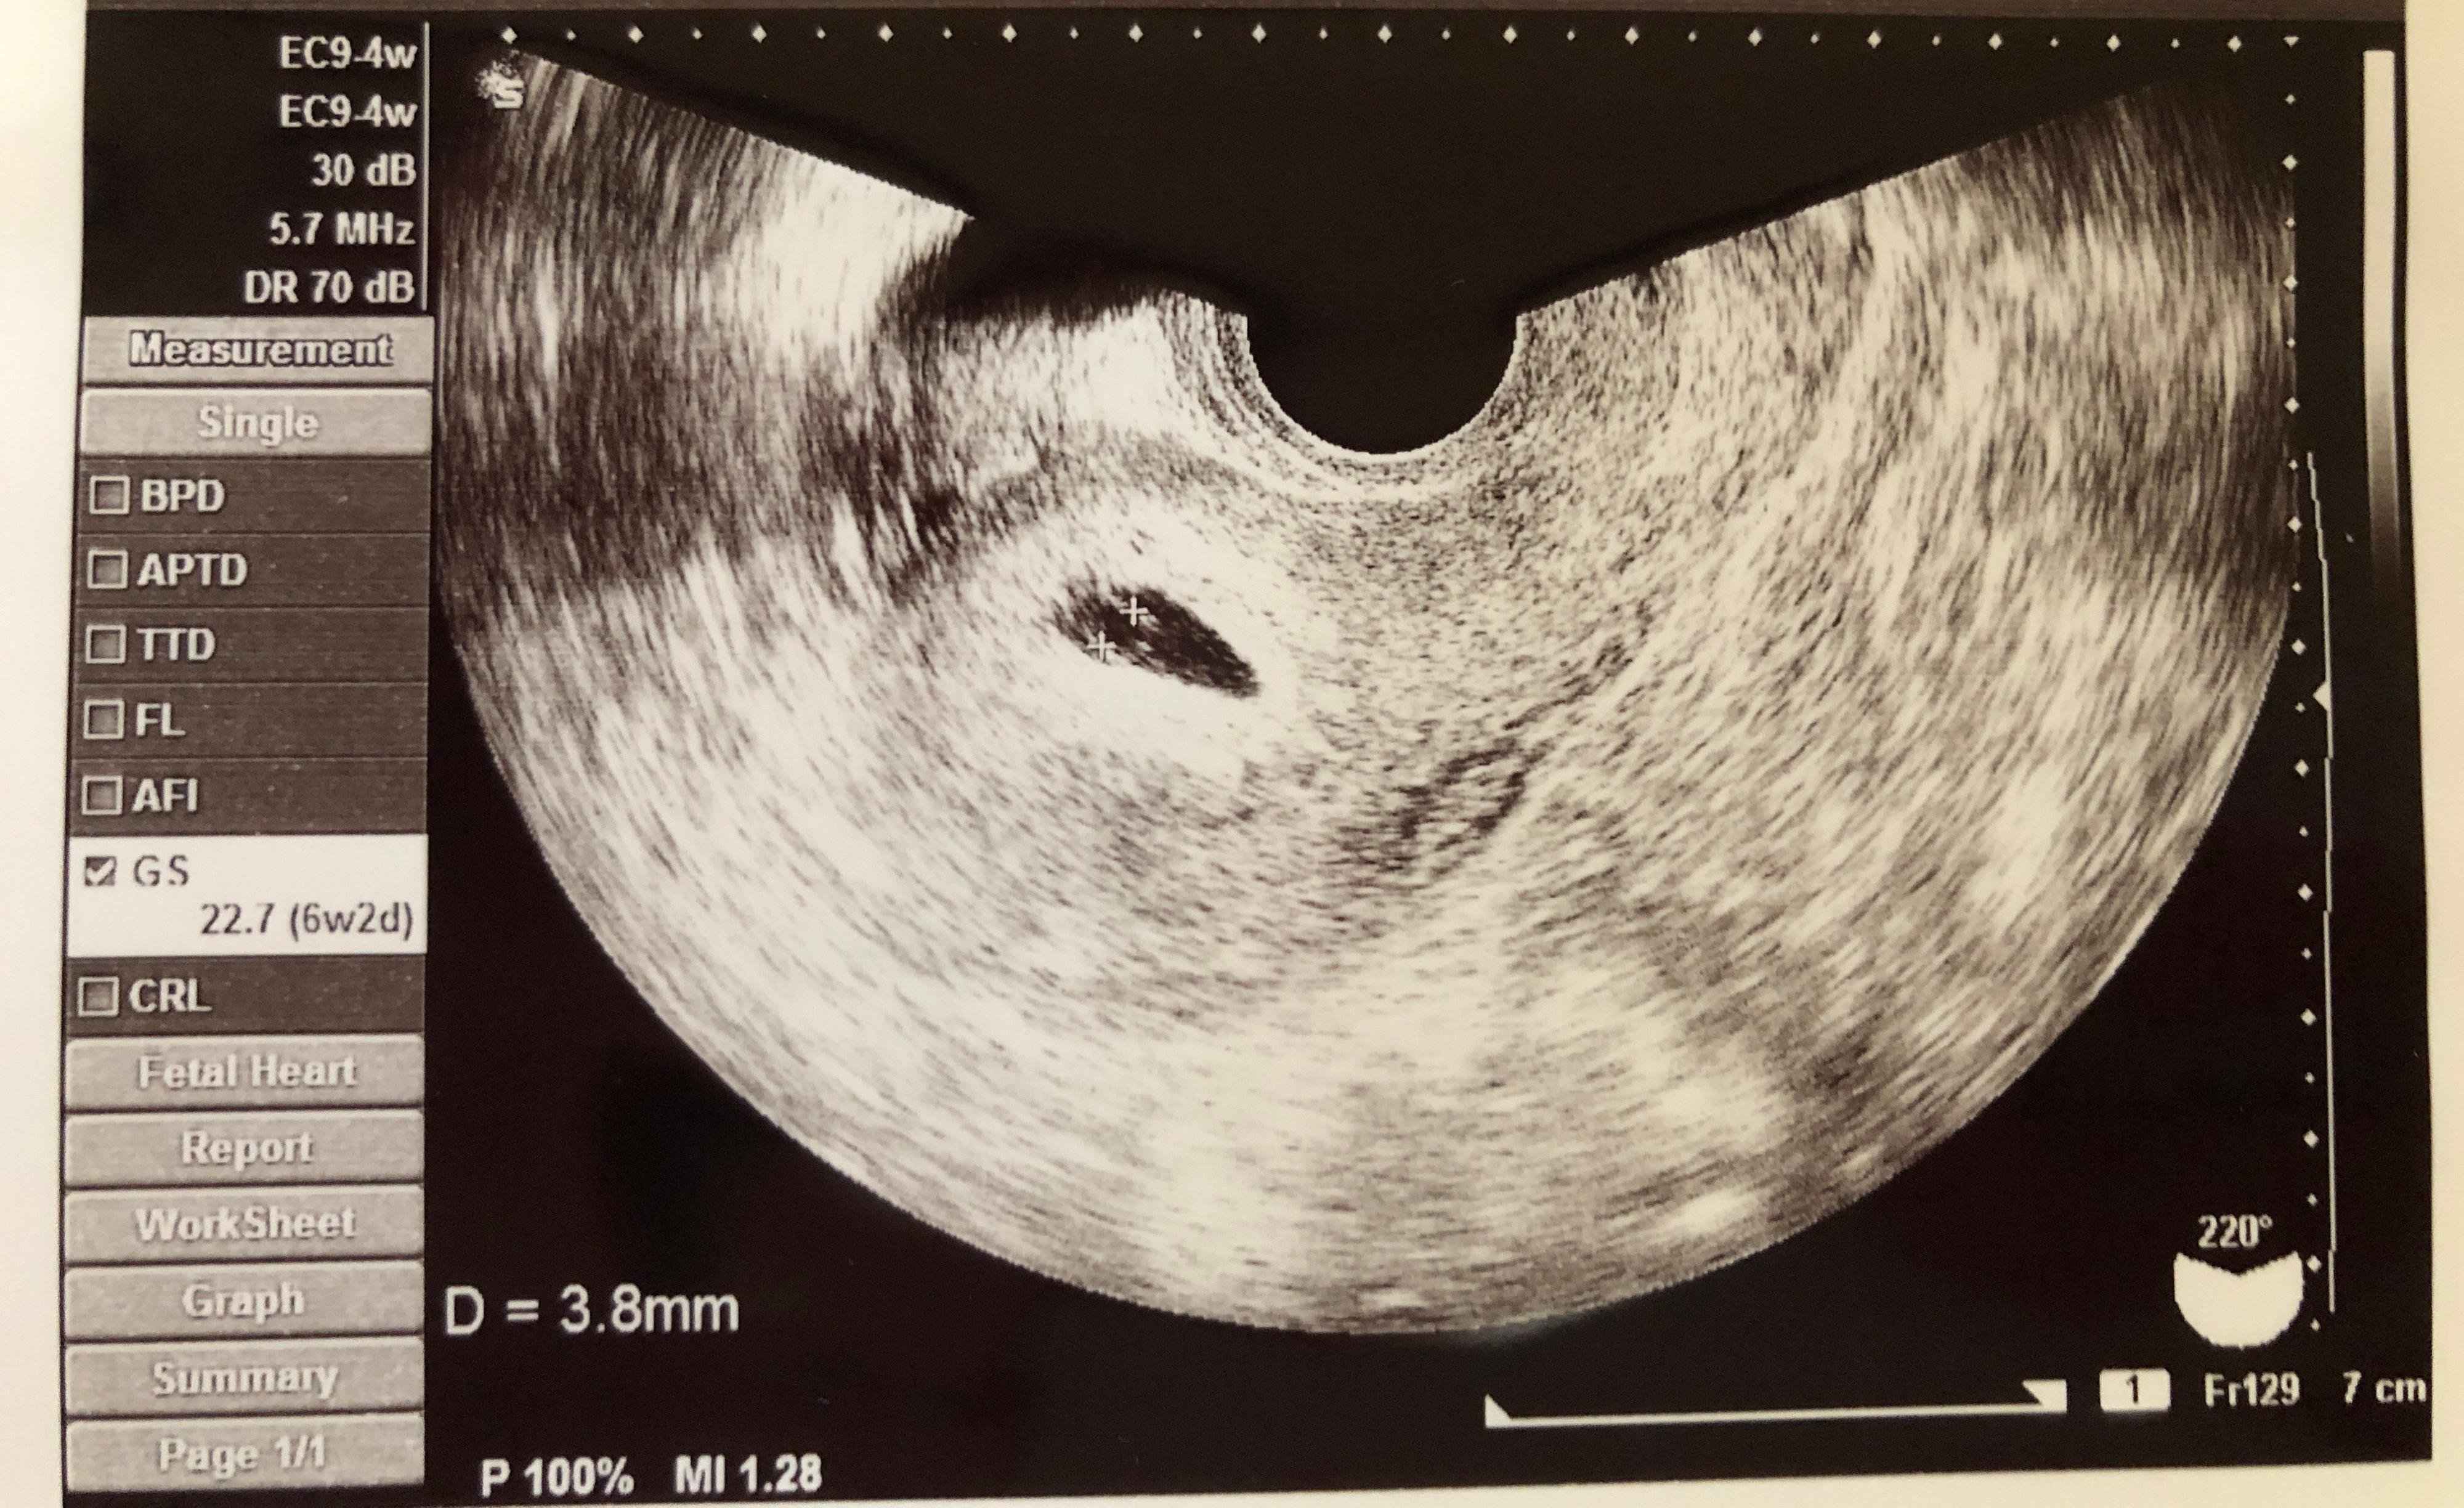

妊娠6週目 驚きの第二子妊娠

長男出産後、1度生理が来て、その翌月は来なかったのですが、ママ友から「産後の生理周期は乱れがち」と聞いていたので、特に気にしていませんでした。でも、なんとなくだるい日が続いたので、試しに妊娠検査薬を使ってみたところ、陽性反応が!

嬉しい反面、まだ小さい長男の授乳などをどうしたらいいのか、戸惑いもありました。翌日病院に行き、先生に相談した結果、長男は完全母乳からミルクへ切り替えることになりました。